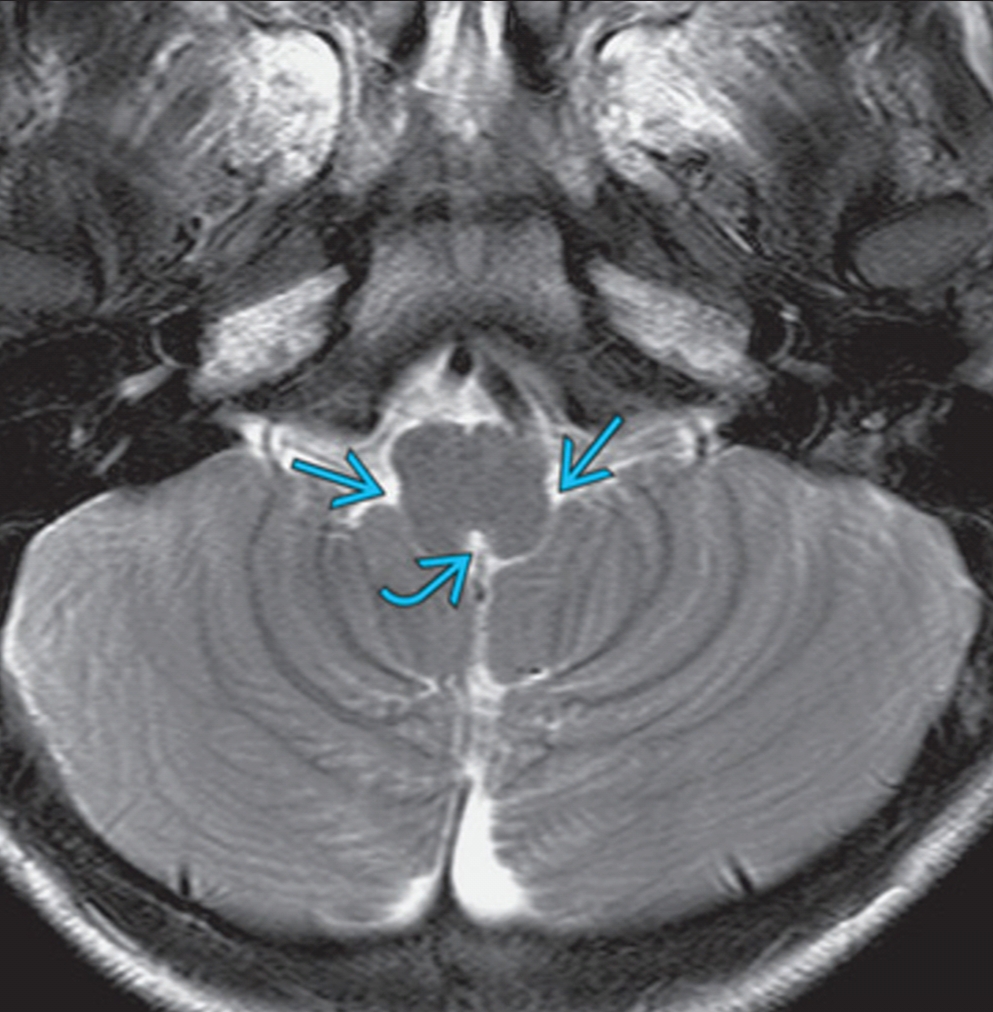

From viewfloor.co

Floor Of 4th Ventricle Mri Viewfloor.co Mri Anatomy Ventricle learn how to use cardiovascular magnetic resonance (cmr) to measure rv mass and systolic function in various pathologies. learn about the cerebral ventricular system, which produces and circulates cerebrospinal fluid in the brain. Explore the anatomy and pathology of the ventricles, thalamus,. the ventricular system consists of four ventricles (spaces), two being midline and the other two. Mri Anatomy Ventricle.